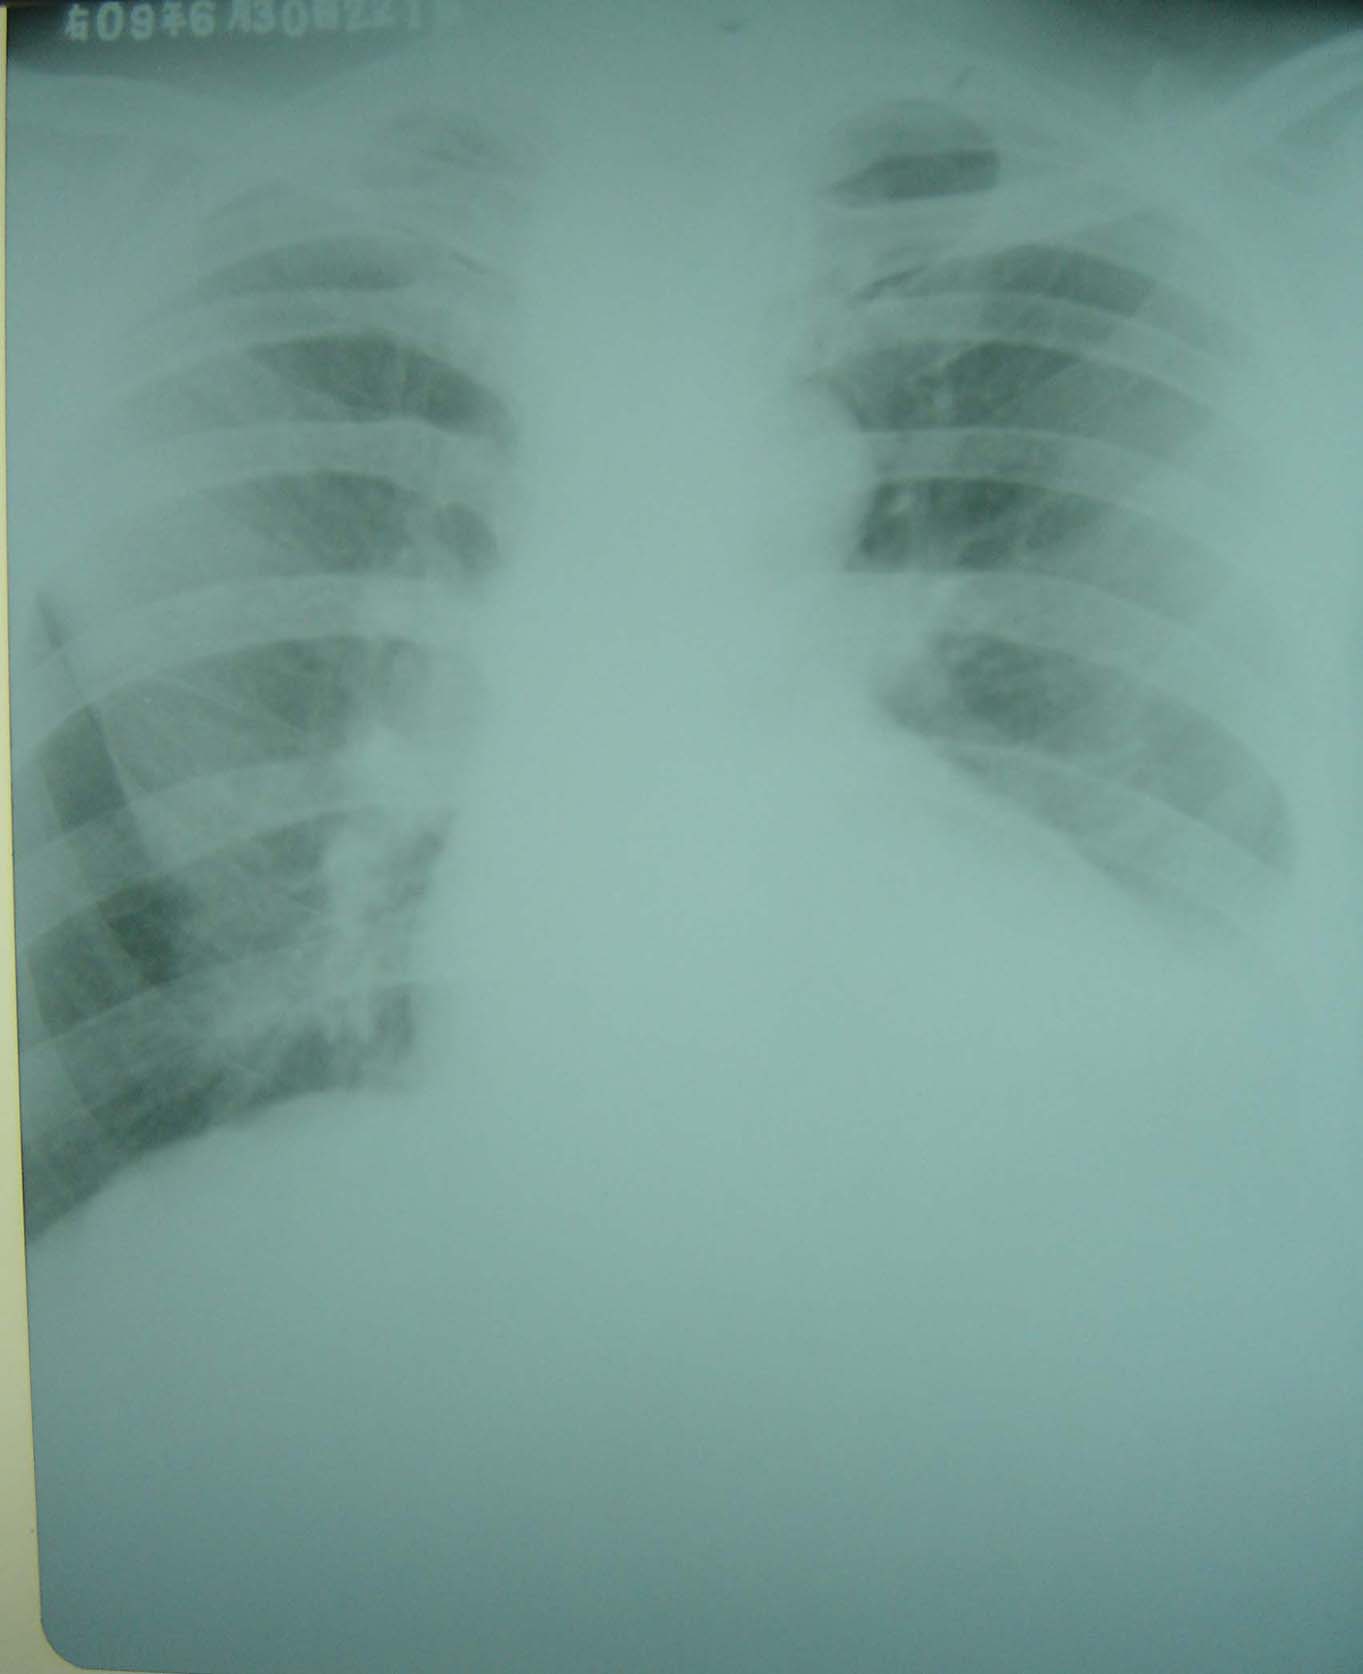

男、75岁、左季肋部疼痛,无其它不适。

左侧少量胸腔积液?左侧输尿管上段结石?片子较模糊,l5si左侧水平好像有条形高密度影。

左侧胸腔积液,左侧输尿管上段结石。

1)左侧胸腔积液?2)左侧输尿管上段结石可能;建议行进一步检查。

左侧少量胸腔积液,左侧输尿管上段结石?